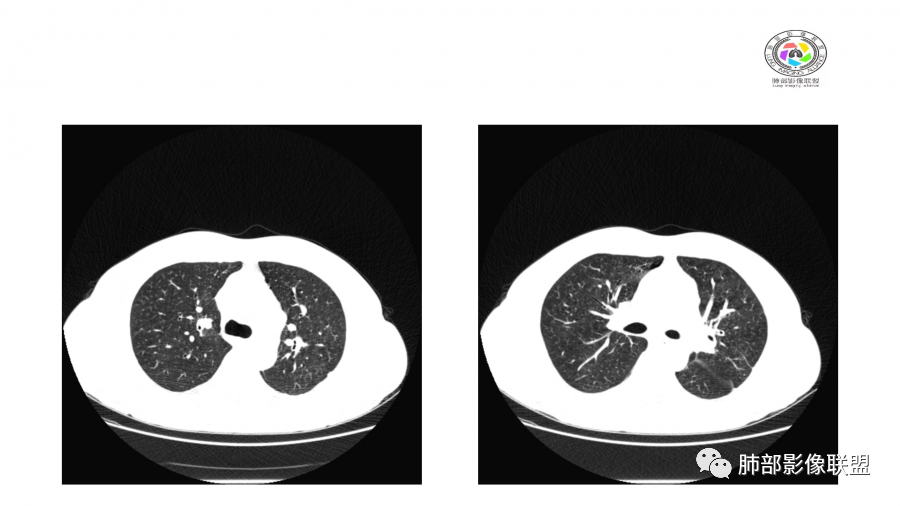

晨读:双肺不均匀分布片状,斑片状影,边缘有晕,部分病灶内见支气管像,密度不均。50多天3次CT复查,病变此起彼伏。考虑病毒>OP>吸入。

晨读:双肺不均匀分布片状,斑片状影,边缘有晕,部分病灶内见支气管征,密度不均。常规考虑OP,但是结核病人肝肾功能,还是考虑真菌,隐球菌可能,其次结核待排。

病史,中年男性,乏力纳差,高血压,肾功能不全,贫血。影像,双肺多结节,斑片影,后期吸收,考虑肺水肿?血管炎?

病灶此起彼伏,肾功异常,部分病灶有晕,考虑肉芽肿性多血管炎。

双肺多发实变及磨玻璃影,边界欠清,部分可见小叶间隔增厚,支气管穿行病灶内,多次随访复查,部分有吸收又似有新发,双侧纵隔淋巴结肿大,临床:男性49岁,肾功能异常,考虑GPA,OP

患者,男,49岁,初次以头晕呕吐肾功能异常入院,后期伴双下肢水肿,CT示双肺多发斑片及结节影,部分周围伴晕,部分内部可见支气管穿行,多次复查可见部分病灶略吸收及新发病灶出现,最后一次复查双肺多发磨玻璃样改变,综合考虑血管炎,最后一次伴肺水肿可能

中年男性,高血压,肾功能衰竭,贫血病史,尿潜血阳性。3.8双肺野多发斑片磨玻璃实变影,结节影,边缘模糊,周围有晕征,内见支气管充气征,主要沿支气管血管束分布,部分胸膜下分布,3.12号病灶有吸收好转,4.8号斑片实变影基本吸收,主要沿支气管血管束分布结节影,边缘平直收缩,4.28病灶大部分吸收好转,双肺支气管血管束增粗,有少量结节影。考虑ANCA相关性血管炎可能性大,第一次片子觉得隐球菌不排除,但是后面没有抗真菌治疗就吸收了,觉得隐球菌可能性不大。

两肺多发团片状高密度影

边界模糊,距离胸膜有间隙,内部支气管通畅